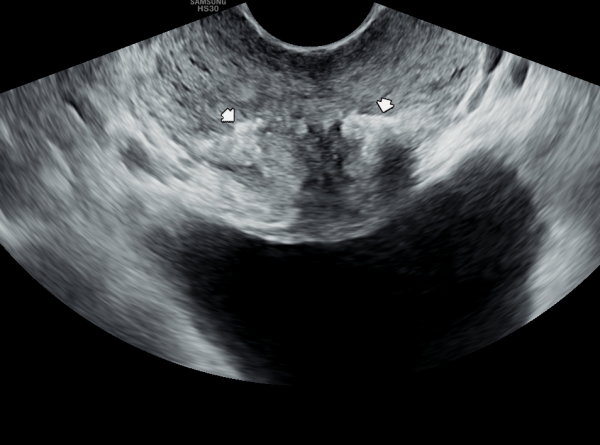

내원 당일 정낭의 경직장 전립선 초음파 검사상 사정관입구의 섬유화와 탈락된 상피 세포 그리고 결석에 의한 폐쇄로 정관을 통한 정자의 순환 장애로 커진 정낭과 혈정액등을 일으키는 초음파 사진입니다.

This is a transrectal prostate ultrasound image of the seminal vesicles taken on the day of the patient's visit. The image shows fibrotic changes

at the ejaculatory duct openings, along with obstructive epithelial debris and calculi, leading to impaired sperm flow through the vas deferens,

resulting in enlarged seminal vesicles and hematospermia.